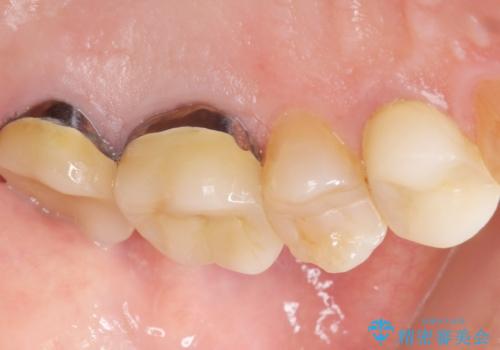

- 歯ぐき(ちょうど根の先のあたり)から膿が出て、根の治療を何度しても治らないことを主訴に来院された患者様です。

精査したところ、奥歯(左上67)の根尖部に位置した歯茎に瘻孔(膿の出口)ができており、CTを撮影し確認すると奥歯2本(左上67)の根尖病変は大きくつながっていました。

銀座しらゆり歯科の林院長による精密根管治療を受けて頂いたのち、メタルボンドクラウンによる補綴を行いました。